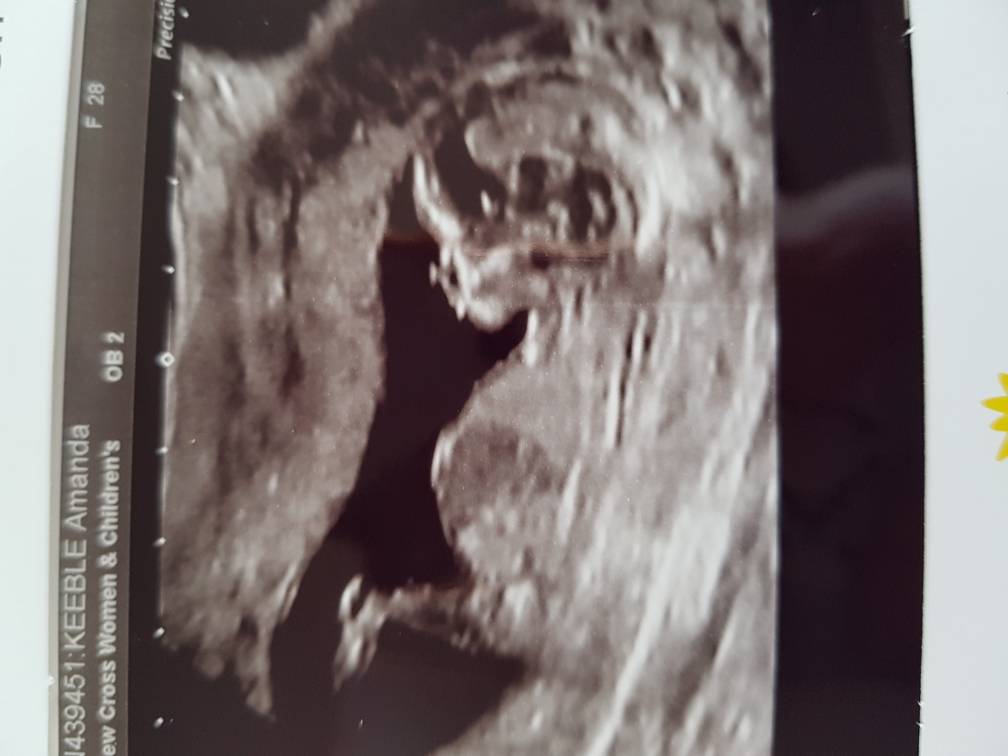

Hi as you can tell I'm ridiculously impatient. I am so eager to find out if I'm having a boy or a girl I've been looking up theories. Looking at the symptoms I've had it edges towards a boy but im assuming those are just old wives tales. The most positive one seems to be the nub theory however I can't seem to see one on ours. This scan as do e at 12 weeks 5 days. Does anyone have any idea on the gender or nub theory? :)Attachment 37902